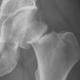

An Australian breaks, snaps or cracks a bone every 3.4 minutes due to poor bone health, a new analysis shows as experts predict rising rates of osteoporosis among our ageing population. More than 155,000 people nationally are expected to break a bone ...